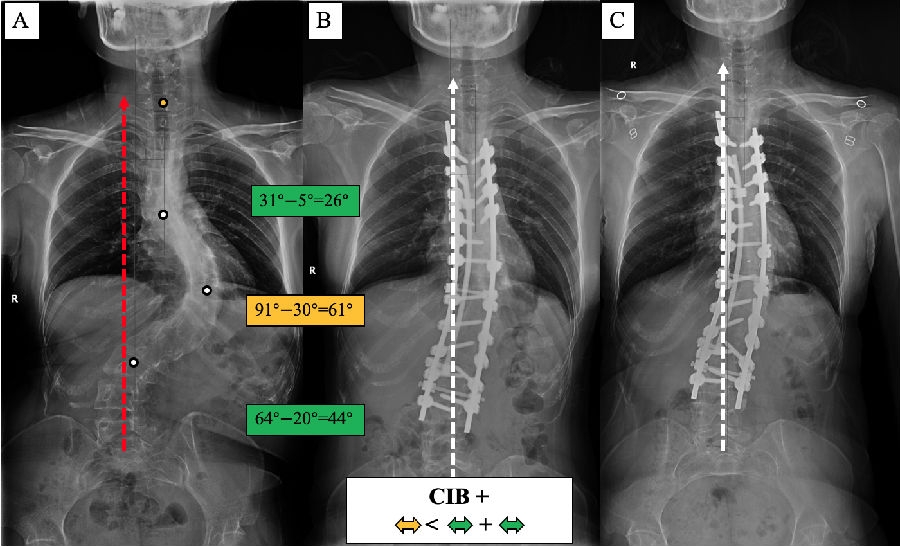

(3) 术前CIB-患者:主弯矫正61°,上胸弯及腰弯矫正分别为33°和21°,术后平衡改善。

(4) 术前CIB+患者:主弯矫正61°,上胸弯及腰弯矫正分别为26°和44°,术后平衡改善。

基于以上临床观察,我们提出了脊柱侧凸顶椎位置分布的冠状面平衡修正[7]。首先,根据CBD是否大于2cm,将患者分为冠状面平衡(coronal balanced, CB)和冠状面失平衡(coronal imbalanced, CIB)。然后,根据患者各个弯曲顶椎/椎间隙中心的分布特点,赋予顶椎位置分布修正(-/+),若果各顶椎中心分布在CSVL两侧,则为修正(-),若各顶椎中心分布在CSVL同侧,则为修正(+)(图7)。

图8. 各类型患者的手术矫形策略。